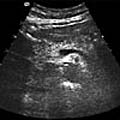

Om ultraljud av bukspottkörteln

Bukspottkörteln (pancreas) undersökes ofta i samband med undersökning av lever och gallvägar. Detta benämns då ofta som en förkortning LGP (lever-galla-pancreas).

Ultraljud är en bra, enkel och smärtfri metod för att påvisa sjukdomar inom bukspottkörteln.

Vid ultraljudsundersökning av bukspottkörteln undersökes oftast gallvägar och lever samtidigt. Detta benämns då ofta som en förkortning LGP (lever-galla-pancreas).